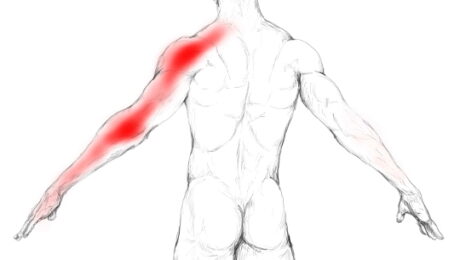

“Une névralgie est une douleur (algie) survenant dans le territoire d’un nerf sensitif (nevr), souvent d’un seul côté. La névralgie cervicobrachiale, ou « sciatique du bras », est une maladie douloureuse due à l’atteinte d’une des racines nerveuses destinées au membre supérieur. Le patient se plaint de douleurs dans le cou et dans le bras. La partie